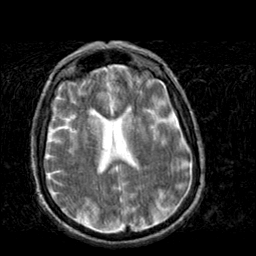

Creutzfeld-Jakob disease: T2-weighted MR -- Slice #14

[Home][Help][Clinical] Slice 14